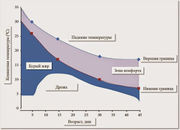

| 12:09, 23 ноября 2015 | Brown adipose tissue4.jpg (файл) |  |

74 КБ | Nico | Бурый жир | 1 |

| 12:07, 23 ноября 2015 | Brown adipose tissue3.jpg (файл) |  |

40 КБ | Nico | Бурый жир | 1 |

| 12:07, 23 ноября 2015 | Brown adipose tissue2.png (файл) |  |

44 КБ | Nico | Бурый жир | 1 |

| 14:13, 22 ноября 2015 | Brown adipose tissue1.png (файл) |  |

96 КБ | Nico | Бурый жир | 1 |